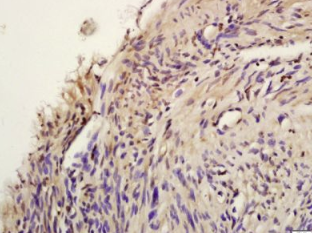

组织/细胞:人子宫肌层组织;4%多聚甲醛固定石蜡包埋;

抗原提取:柠檬酸缓冲液(0.01M,pH 6),15min煮沸,用3%过氧化氢阻断内源性过氧化物酶30min;37℃下阻断缓冲液(正常山羊血清)20 min;

孵育:抗磷-AKT1(Tyr474)多克隆抗体,未结合 1:200,在4°C下过夜,然后接合到二级抗体和DAB染色。